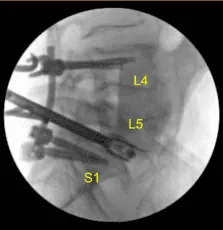

El paciente estaba cubierto de forma estéril. Se realizó una tomografía computarizada intraoperatoria y los datos se transfirieron al ordenador de neuronavegación. Se verificó la precisión y se utilizaron técnicas de neuronavegación para colocar tornillos pediculares bilateralmente en los pedículos L4, L5 y S1.

Comenzamos a decorticar con un taladro eléctrico de alta velocidad y un rongeur Leksell, cenulamos bilateralmente los pedículos de L4 con el localizador de pedículos navegados, palpamos para detectar brechas y medimos las profundidades. Usamos una grieta de 5,0 mm y colocamos tornillos pediculares de titanio de 6,0 x 45 mm usando navegación sin dificultad.

A continuación, colocamos los tornillos pediculares bilaterales S1 de la misma manera usando técnicas de neuronavegación. Cuatro puntos de partida e identificación de trayectoria, canulación del sacro, palpamos, sub-roscamos 2 mm usando un tapón de 5,0 mm y luego colocamos tornillos de 7 mm x 40 mm sin dificultad. Las señales de neuromonitorización se mantuvieron estables. En ese momento no pusimos los tornillos L5.

Se repitieron las radiografías para confirmar la posición y el tamaño correctos. Las señales de neuromonitorización se mantuvieron estables. A continuación, con el pedículo L5 izquierdo completamente aislado y expuesto, colocamos el tornillo pedicular izquierdo L5 decorificando con una canulación eléctrica de alta velocidad con el buscador curvo de pediculares Lenke a mano alzada palpando las brechas usando un tap de 5,0 mm y colocando sin dificultad un tornillo pedicular de titanio de 45 mm x 6,0 de diámetro.

Luego colocamos de forma similar un tornillo pedicular derecho L5 usando una técnica similar. Cubrimos al paciente de forma estéril y realizamos una tomografía computarizada intraoperatoria que mostró la correcta posición de todos los tornillos pediculares y el espaciador intersomal.